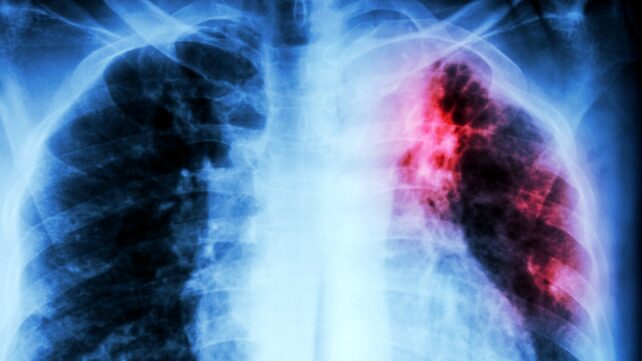

After decades of decline in the developed world, tuberculosis (TB) is back on the rise, and increasingly resistant to our best antibiotics.

Tuberculosis is now claiming well over a million lives every year, and can be spread through airborne droplets (from coughing or breathing). While the disease is curable, effective treatments are not universally available. A full course of TB-fighting drugs can take months to fully work, which may contribute to the emergence of antibiotic-resistant strains.